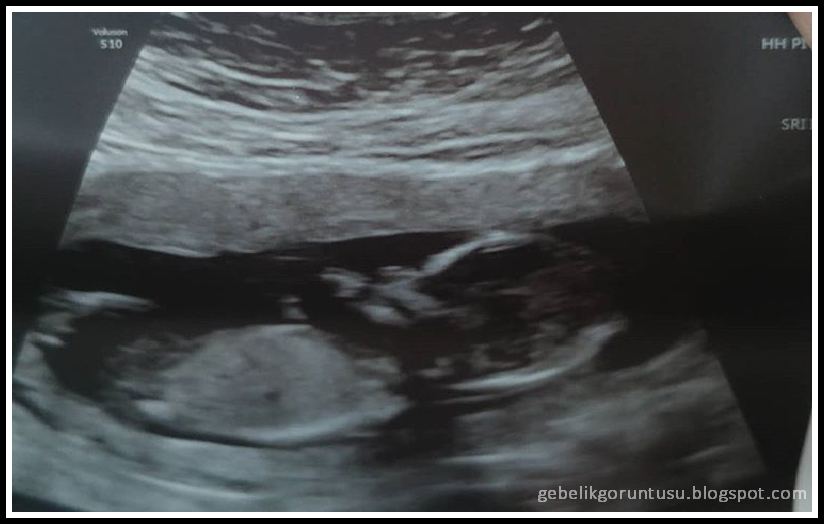

14 haftalık gebelik ultrason görüntüsü

| 14 Haftalık Gebelik (Hamilelik) Görüntüsü |